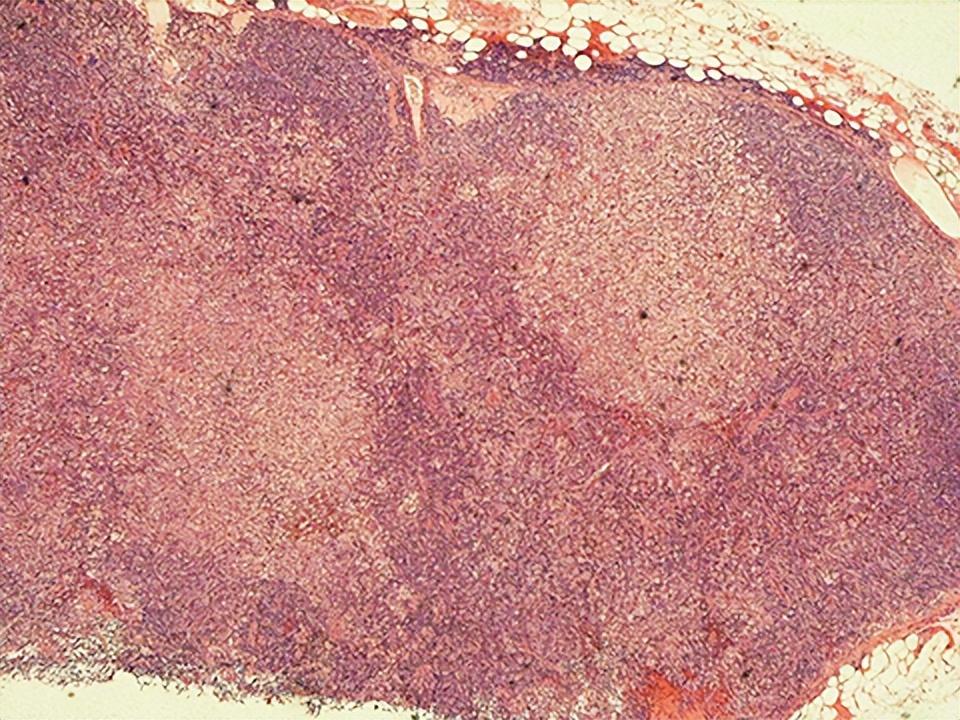

菊池病的淋巴结活检(淋巴结活检病理学提示淋巴结炎,表现为斑片状皮质旁和皮质坏死,伴有丰富的核碎屑。坏死灶周围有广泛的组织细胞浸润,有不同程度的免疫母细胞和淋巴细胞。主要的淋巴细胞是CD8+T细胞)